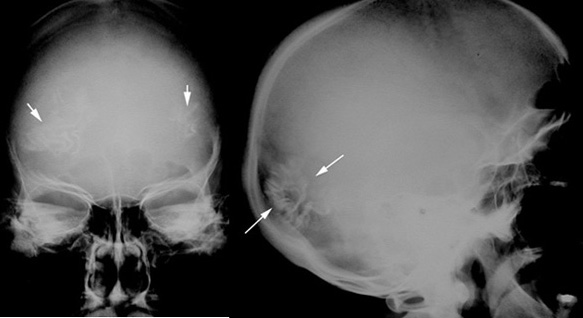

Sturge Weber Syndrome

• Arrows point to bilateral "tram track like" calcification in the parieto occipital regions. These calcifications are typically seen in Sturge Weber Syndrome.

• Calcifications are in the hemangiomas in the brain.